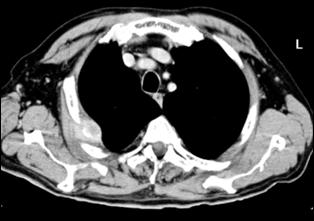

Cele mai multe metasteze la distanta, provocate de tumorile vezicale maligne, sunt localizate in plamani si in oase. Diagnosticul acestora se face prin: radiografii toraco-pulmonare, radiografii osoase sau scintigrame osoase (evidentiaza metastazele osoase cu 9-12 luni mai devreme decat expresia evidenta a acestora pe radiografiile standard).

4.5. Radiografia osoasa 4. Radiografia toraco-pulmonara

Figura 44. Metastaza in articulatia coxo-femurala

dreapta Figura 45. Metastaze pulmonare multiple dintr-un carcinom vezical

infiltrativ.

a. b.

Figura 4 Radiografie toraco-pulmonara cu metastaze pulmonare multiple

dintr-un carcinom vezical infiltrativ

Figura 47. Radiografie toraco-pulmonara cu metastaze pulmonare multiple dintr-un carcinom vezical infiltrativ.